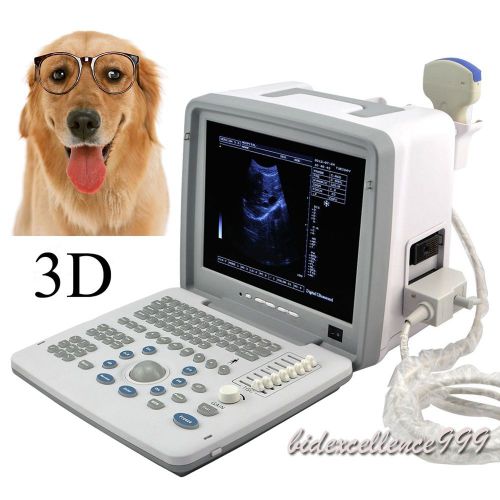

Model | 9000BV |

| Screen Size | 12 Inch | ||

| Machine Size | 31cm*21cm*27cm | ||

| Image resolution | 800*600 | ||

| Probe | Rectal probe | ||

| Options | Linear / Convex / Micro-Convex |

12" LCD Portable Digital Ultrasound Scanner 3.5Mhz Convex Probe 3D Veterinary CE